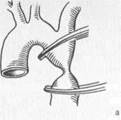

Чрескожная транслюминальная баллонная ангиопластика (эндоваскулярная дилатация). Современные приспособления для чрескожной транслюминальной ангиопластики представляют собой жесткий баллон, способный выдерживать давление в 5—20 атм, смонтированный на двухканальном катетере (один канал предназначен для введения контраста и перемещения катетера по проводнику, другой — для раздувания баллона). Под рентгенотелевизионным контролем в просвет артерии вводится проводник, который продвигается в дистальные отделы к суженному участку. По проводнику вводят баллонный катетер. Установив баллон в зоне сужения, в нем повышают давление с помощью жидкости и достигают дилатации сосуда (рис. 18.4). Патоморфологический механизм, на котором основана баллонная ангиопластика, состоит в разрыве и фрагментации либо механическом раздавливании атеросклеротической бляшки, растяжении артериальной стенки. Вызванные дилатацией повреждения стенки сосуда постепенно заживают, а просвет артерии остается более широким в течение длительного периода. Суть метода лазерной ангиопластики состоит в реканализации артерии путем выпаривания атероскле-ротических бляшек. Для их удаления используют также артерэктомические катетеры, позволяющие удалять бляшки со стенок артерии, и роторную ди-латацию, при которой бляшки из суженного участка артерии "высверливают" роторным катетером и таким образом восстанавливают магистральный кровоток.

В последнее десятилетие широкое применение в клинической практике получили методы эндоваскулярной установки стента или эндопротеза. Стенты представляют собой тонкую сетку из металлических нитей. Будучи смонтированными на специальном приспособлении (например, на баллонном катетере), стенты в свернутом состоянии вводят в стенозированныи участок артерии под рентгенотелевизионным контролем. Затем после расширения сосуда баллоном стент сдвигают с проводника. В суженном участке он расширяется (рис. 18.5). Расширенный металлический стент обладает достаточной прочностью для того, чтобы выдержать противодействие артериальной стенки и сохранить достигнутое расширение просвета сосуда. Эндопротез представляет собой герметичное устройство из плотного синтетического материала. Верхний и

Рис. 18.4. Баллонная ангиопластика (схематическое изображение).

Рис. 18.5. Эндоваскулярная установка стента (схематическое изображение).

нижний концы его имеют специальные крюч-ковидные шипы, с помощью которых они при расправлении стентом прочно фиксируются к артериальной стенке. Эндопротезы вводят через артериотомическое отверстие. Они используются при аневризме артерий для выключения аневризматического мешка из циркуляции. Эндопротез позволяет избежать открытого вмешательства на самой аневризме;

при лечении окклюзионных поражений может ограничивать гиперплазию интимы вдоль оси реконструируемого сосуда.